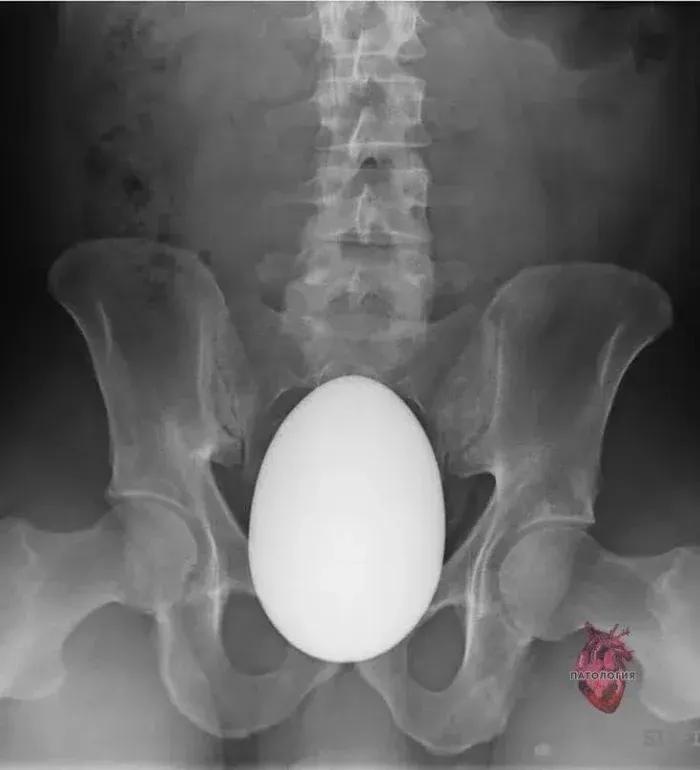

塞进去的东西就比较五花八门了,沐浴露、胡萝卜、鸵鸟蛋、水果刀、啤酒瓶,甚至还有活物……

由于部位的私密性,很多患者往往不会坦白病情,“每次接诊,就像是在开盲盒”。

一位不愿意透露姓名的肛肠科大夫表示:“除了孩子,好像啥都取出来过。”

塞进去的异物就比较难治疗了,一般是先需要医生进行肛门指检,再选择适宜的手术方式。通俗点说,就是手掏大便,看看异物深浅。